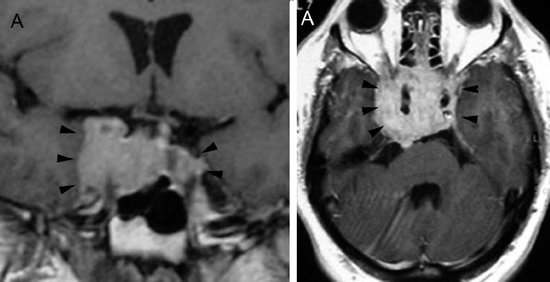

En el caso de los microadenomas, al ser tumores funcionantes, el cuadro clínico y de laboratorio ayuda a definir la localización de la lesión. La glándula pituitaria, considerando el pequeño tamaño de los tumores, puede mostrar forma y volumen normal. En un 20-25% de los casos no se logra demostrar los microadenomas menores de 3 mm, lo que aumenta al 40% en el casos de los adenomas productores de ACTH, en que los exámenes falsos negativos son más frecuentes36-38 (Figuras 11A, 11B, 11C y11D). En este grupo de pacientes es fundamental la utilización de protocolos de examen que incluyan cortes finos coronales de 1 mm en secuencias ponderadas en T1 antes, durante y después de la inyección de Gadolinio, para asegurar la detección de los adenomas, los cuales se contrastan en general más tardíamente que la glándula normal39-41 (Figuras 12A y 12B).

Figura 11A. Microadenoma pituitario productor de ACTH, corte coronal, secuencia T1w, muestra señal homogénea en la hipófisis. B. corte coronal (secuencia dinámica T1w con Gadolinio); se observa nódulo hipointenso de 3 mm (que aun no se refuerza) en cuadrante inferolateral izquierdo de la hipófisis (punta de flecha). C. corte coronal, secuencia tardía T1w con Gadolinio, muestra refuerzo heterogéneo de la glándula, no es posible precisar la ubicación del tumor. D. corte coronal, secuencia volumétrica SPGR T1w con Gadolinio de 1 mm de espesor, que muestra claramente la ubicación del tumor (punta de flecha). Esta secuencia ha mostrado mejores resultados en la evaluación de la enfermedad de Cushing.